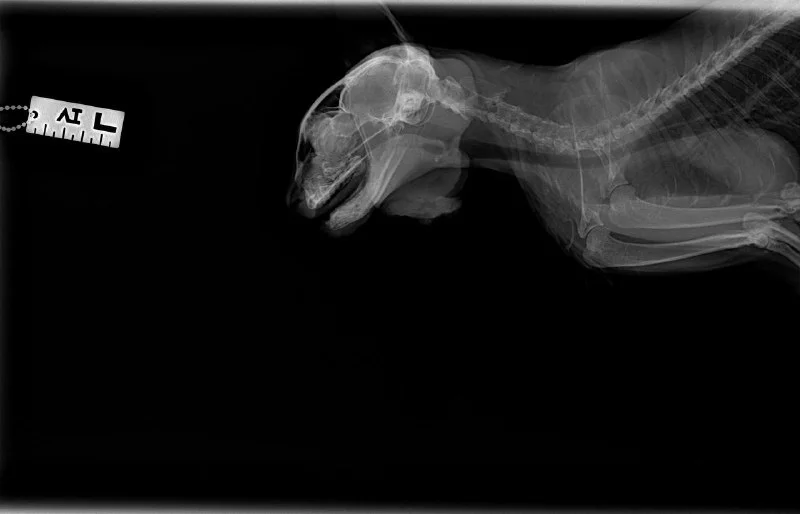

Так выглядит качественная стерилизация у девочек